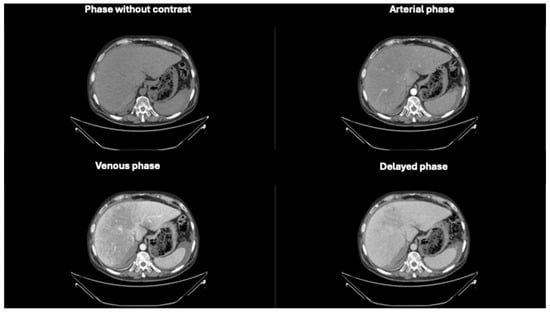

Figure 5. Axial CT images in different phases, highlighting extravasation of contrast medium within the subhepatic fluid collection. In the venous and delayed contrast-enhanced phases, a difference in the density of the perihepatic fluid collection is observed, indicating ongoing active bleeding. The lower border of the liver shows a blurred contour, especially evident along its inferior surface [3].